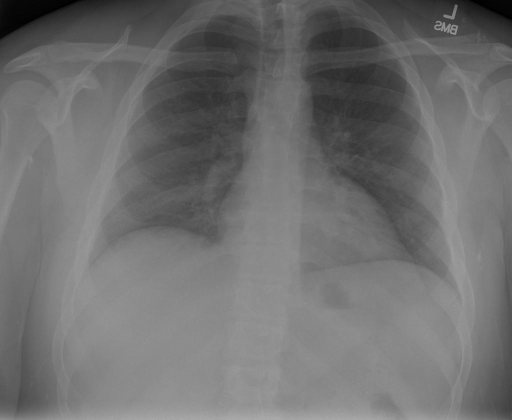

- (1)准备[诊疗报告(中文)](./data/Xray/openi-zh.json)和[X光影像](https://pan.baidu.com/s/13GBsDMKf6xBZBSHpoWH_EA?pwd=k9sh)在`data/Xray`文件夹下; - (2)开始训练: ```bash # 设置CUDA变量,主要是为了解决有时候直接训练而出现无法正确加载到显卡问题 export CUDA_VISIBLE_DEVICES=0,1,2,3 # 开始训练 bash finetune_XrayGLM.sh ``` 这里的复现过程非常简单,主要是很多过程我们都为大家准备好了,大家可以随时复现一个自己的`XrayGLM`。 ### 4.模型训练(通用) ## 效果展示 *以下效果来自于**低质量**的数据训练和权重 影像诊断: |X光影像|诊疗报告(医生)|XrayGLM| |:-|:-|:-| |![](./data/Xray/2_1.png)|根据X射线图像,心脏大小正常,肺部看起来很清晰。已经排除了肺炎、积液、水肿、气胸、腺病、结节或肿块的存在。该发现表明一切正常。换句话说,总体印象是胸部正常。|X光片显示,心脏大小正常。肺部没有气胸或胸腔积液的证据。骨骼结构看起来没有任何异常。总的来说,X光片表明没有发现急性心肺疾病的迹象。| |![](./data/Xray/2882_1.png)|X光图片显示没有扭曲的区域、可疑的骨质不透明度或胸腺积液。心脏大小轻微增大,但非常稳定。此外,没有气胸的证据,肺野也正常。总体来说,X光片显示没有急性心脏异常,但要注意轻微的心脏扩大。|X光片显示,心脏大小正常。肺部和纵隔轮廓清晰,没有气胸或胸腔积液的证据。骨骼结构完整,没有任何急性异常。| |![](./data/Xray/2577_1.png)|心影形态在正常范围内。没有急性骨质异常。有可能出现没有明显的吸水或肺实质状况的线索。没有大面积积液或气胸。有可能怀疑其有误吸或肺实质问题。为了确诊和治疗,可能需要进行适当的影像学随访。|心脏大小正常,肺部和纵隔轮廓清晰。没有急性异常或活动受限的证据。没有任何明显的气胸、胸腔积液或肺不张的迹象。此外,也没有发现任何局灶性骨质异常或其他急性疾病。| 多轮对话: |X光影像|诊疗报告(医生)| |:-|:-| |![](./data/Xray/861_1.png)|右侧主动脉突出观察到。心脏大小正常。胸部未发现明显的肺气肿、胸膜积液或可疑的肺部病变。报告指出已知右侧主动脉情况正常。| ```bash >> X光影像路径:./data/Xray/861_1.png >> 用户:这是一张什么图? >> XrayGLM:这张图片显示的是一张肺部检查的X光片。 >> 用户:请描述这张胸部X光片的诊断结果 >> XrayGLM:心脏大小正常,肺部清晰。没有急性心肺疾病的证据。 >> 用户:是否存在肺气肿? >> XrayGLM:没有肺气肿。心脏大小正常,肺部清晰。没有发现急性心肺疾病的证据。 >> 用户:平时饮食该注意什么? >> XrayGLM:饮食应该健康,均衡。建议增加蛋白质的摄入量,因为蛋白质有助于维持肌肉和骨骼的健康。多食用蔬菜、水果、全谷物以及健康的脂肪来源如橄榄油、鱼类等可以帮助获得足够的维生素和矿物质。此外,避免过度饮酒或吸烟,这些习惯可能会对心脏健康产生负面影响。 ``` ## 未来展望 1. 模型的能力更多来源于数据的支持,`OpenI-zh`作为微调数据集,其数据量足以支持研究,在更广泛的任务和性能表现上,我们认为**在大规模数据集上预训练并在高质量少量数据集上微调是一种可行的方案**; 2. 普遍意义的理解上,视觉多模态模型=视觉模型+语言模型。除了需要关注视觉模型信息与语言模型输出的搭配外,还需要**额外关注到语言模型的加强,在人机的对话中,尤其是医疗语言模型的问答上,除了专业的医疗问题回答,带有人文情怀的有温度的回答更应该是我们追寻的目标**。 3. **高精度的模型永远打不过大参数的模型**,如果在6B模型和13B模型上选择微调,请在资源充足情况下选择13B的大参数模型; ## 项目致谢 1. [VisualGLM-6B](https://github.com/THUDM/VisualGLM-6B)为我们提供了基础的代码参考和实现; 2. [MiniGPT-4](https://github.com/Vision-CAIR/MiniGPT-4)为我们这个项目提供了研发思路; 3. ChatGPT生成了高质量的中文版X光检查报告以支持XrayGLM训练; 4. [gpt_academic](https://github.com/binary-husky/gpt_academic)为文档翻译提供了多线程加速; 5. [MedCLIP](https://github.com/RyanWangZf/MedCLIP) 、[BLIP2](https://huggingface.co/docs/transformers/main/model_doc/blip-2) 、[XrayGPT](https://github.com/mbzuai-oryx/XrayGPT) 等工作也有重大的参考意义; ![](./assets/images/mpu.png) 这项工作由[澳门理工大学应用科学学院](https://www.mpu.edu.mo/esca/zh/index.php)硕士生[王荣胜](https://github.com/WangRongsheng) 、[段耀菲](https://github.com/IsBaSO4) 、[李俊蓉](https://github.com/lijunrong0815)完成,指导老师为檀韬副教授、[彭祥佑](http://www.patrickpang.net/)老师。 *特别鸣谢:[USTC-PhD Yongle Luo](https://github.com/kaixindelele) 提供了有3000美金的OpenAI账号,帮助我们完成大量的X光报告翻译工作 ## 免责声明 本项目相关资源仅供学术研究之用,严禁用于商业用途。使用涉及第三方代码的部分时,请严格遵循相应的开源协议。模型生成的内容受模型计算、随机性和量化精度损失等因素影响,本项目无法对其准确性作出保证。即使本项目模型输出符合医学事实,也不能被用作实际医学诊断的依据。对于模型输出的任何内容,本项目不承担任何法律责任,亦不对因使用相关资源和输出结果而可能产生的任何损失承担责任。 ## 项目引用 如果你使用了本项目的模型,数据或者代码,请声明引用: ```bash @misc{wang2023XrayGLM, title={XrayGLM: The first Chinese Medical Multimodal Model that Chest Radiographs Summarization}, author={Rongsheng Wang, Yaofei Duan, Junrong Li, Patrick Pang and Tao Tan}, year={2023}, publisher = {GitHub}, journal = {GitHub repository}, howpublished = {\url{https://github.com/WangRongsheng/XrayGLM}}, } ``` ## 使用许可 此存储库遵循[CC BY-NC-SA](https://creativecommons.org/licenses/by-nc-sa/4.0/) ,请参阅许可条款。